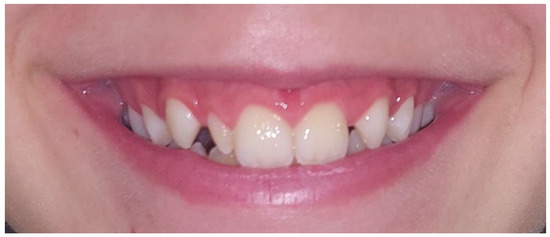

The studies by Backman and Wahlin [18], Ling et al. [19] and Hua et al. [20] reported that the overall prevalence of peg-shaped maxillary permanent lateral incisor was 0.8%, 1% and 1.8%, respectively. The prevalence in our study was higher (2.3%) due to orthodontic samples. Hua et al. [20] reported that prevalence of peg-shaped PMLI varies by race, population and sex. The prevalence rates were higher among Mongoloid people, orthodontic patients and women. The prevalence rates were higher in orthodontic patients (2.7%) than in the general population (1.6%) and dental patients (1.9%) which is in agreement with our study. They also reported that prevalence rates of unilateral and bilateral peg-shaped incisors were approximately the same. However, among the unilateral PMLI, the left side was twice as common as the right side and in addition, contralateral PMLI hypodontia was seen in 55.5% of the subjects with unilateral PMLI. In contrast, Ijaz et al. [21] reported that peg-shaped PMLI was found more common bilateral (53.7%), followed by right side (24.4%) and left side (22.0%). In present study, the prevalence of peg-shaped PMLI was higher in comparison with previous studies [17,18,19,20]. We also found higher rates of unilateral (69.2%) than bilateral (30.8%) peg-shaped incisors, and among the unilateral side, left PMLI was more common affected (52.9%). In present study was found 5 (55.6%) subjects with unilateral peg-shaped PMLI and contralateral hypodontia of PMLI what is in agreement with study by Hua et al. [20]. In present study, statistically significant more subjects with peg-shaped PMLI needed additional dental specialist to achieved satisfactory aesthetics and occlusion than subjects with other crown shape. Unilateral peg-shaped PMLI and even more often unilateral hypodontia, may cause midline asymmetry which together with space (gaps) leads to an unattractive smile (Figure 6). The treatment generally requires an interdisciplinary approach which mean a combination of the orthodontic managements and restorative dentist or prosthodontist. Important factors in determining treatment planning are the age of the patient, the size of the crown and space. There are two basic approaches to treat peg-shaped PMLI. First, to open the space orthodontically for a normal-sized PMLI and then restorative dentist build up the PMLI to simulate a normal-sized PMLI. The second option is to extract PMLI and the resultant space close. In present study, in 12 (92.3%) subjects PMLI were treated conservatively to open space and simulate a normal PMLI, and in one (7.7%) subject the PMLI were extracted, space closed orthodontically and canines reshaped in PMLI.

Figure 6. Unattractive smile due to midline asymmetry and space (gaps) caused by right peg-shaped PMLI and hypodontia of left PMLI.